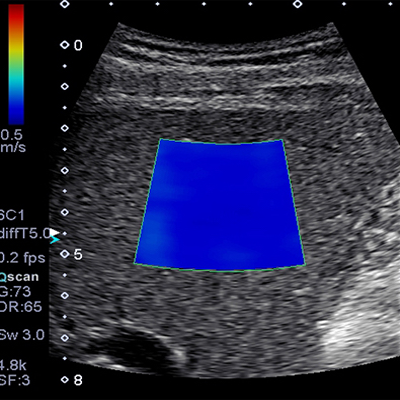

L’élastographie (Shearwave) est une technique récente de l’échographie. Elle étudie les propriétés élastiques et la rigidité des tissus biologiques.

Dans cette modalité d’imagerie, nous étudions la vitesse de propagation d’une onde de cisaillement au sein des structures. Une cartographie relative à l’élasticité des tissus examinés est générée.

Nos échographes sont équipés de la technique la plus récente, par onde de cisaillement. Cette onde est directement générée par la sonde d’échographie. Elle se propage de façon parallèle aux plans cutanés. Sa vitesse de déplacement ne dépend pas de la pression exercée par le médecin. Il s’agit d’une technique reproductible.